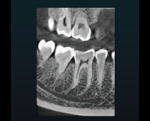

口腔内を高画質で再現することができるため、より正確な診断が可能です。

3Dでの撮影が可能なため、顎の骨の状態(密度・深さなど)を把握することができます。

広範囲で3D撮影を行うことで、歯ぐきの状態を把握することができます。

歯の根の形態や先端の方向など、細部の把握が可能です。